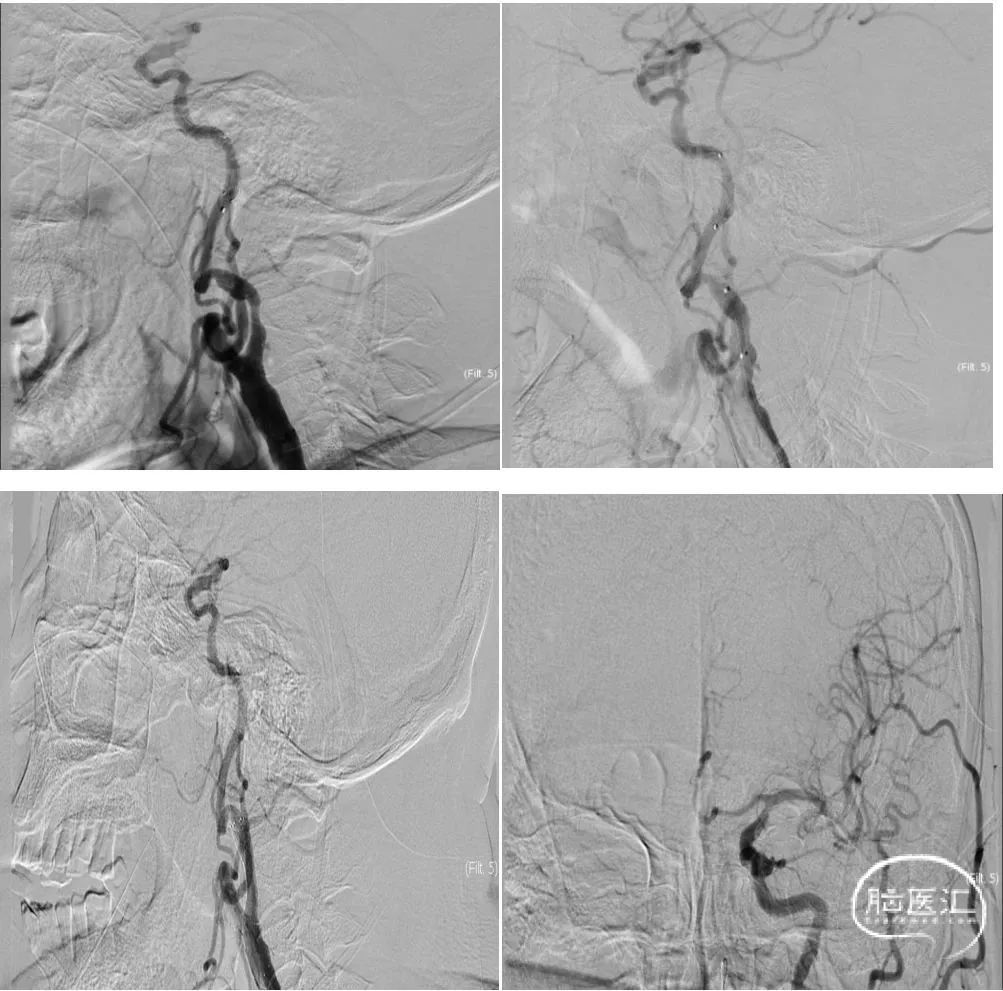

0.014微导丝通过颈动脉闭塞处,采用3.0*20mm心玮披荆颈动脉球囊扩张导管预扩张。

心玮通堑远端通路导管通过颈动脉起始病变处,反复抽吸后造影,大脑中动脉M1段闭塞,微导管及微导丝通过病变后撤出微导丝,通过微导管造影明确闭塞远端。

释放6*30mm心玮捕星颅内取栓支架,采用SWIM技术进行取栓,大脑中动脉再通良好,大脑前动脉A3段存在血栓逃逸(红色箭头),动脉团注替罗非班注射液10ml。

释放心玮灵笼栓塞保护器,采用5*30mm心玮披荆颈动脉球囊扩张导管再次进行扩张,随后释放6-8*40mm颈动脉支架,再次通过导引导管造影,血管再通良好。